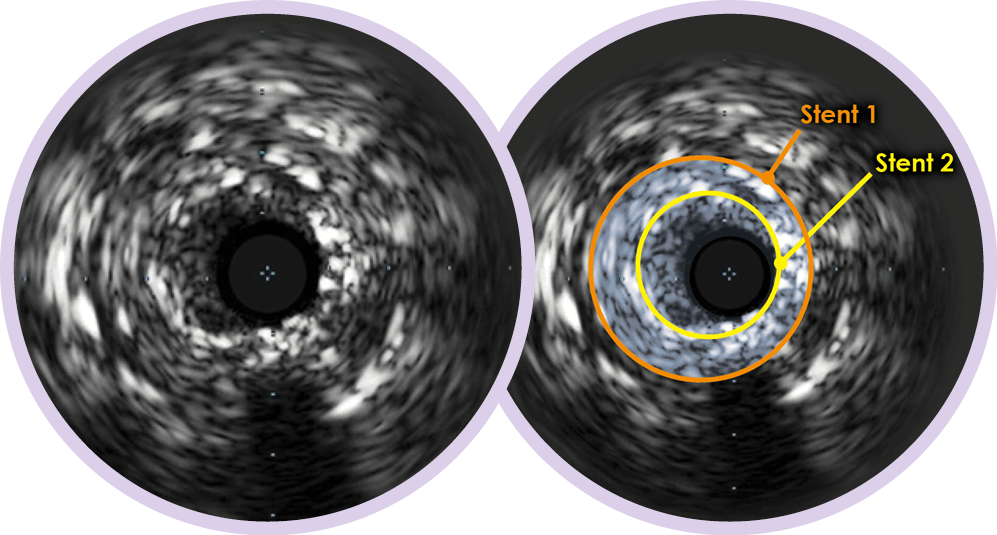

IVUS may help to determine: • Extent and mechanism of restenosis for optimal treatment strategy and for the decrease of risk of geographic miss • Location and amount of thrombus

IVUS is an AHA/ACC/SCAI Class IIa recommendation to determine the mechanism of stent restenosis.9